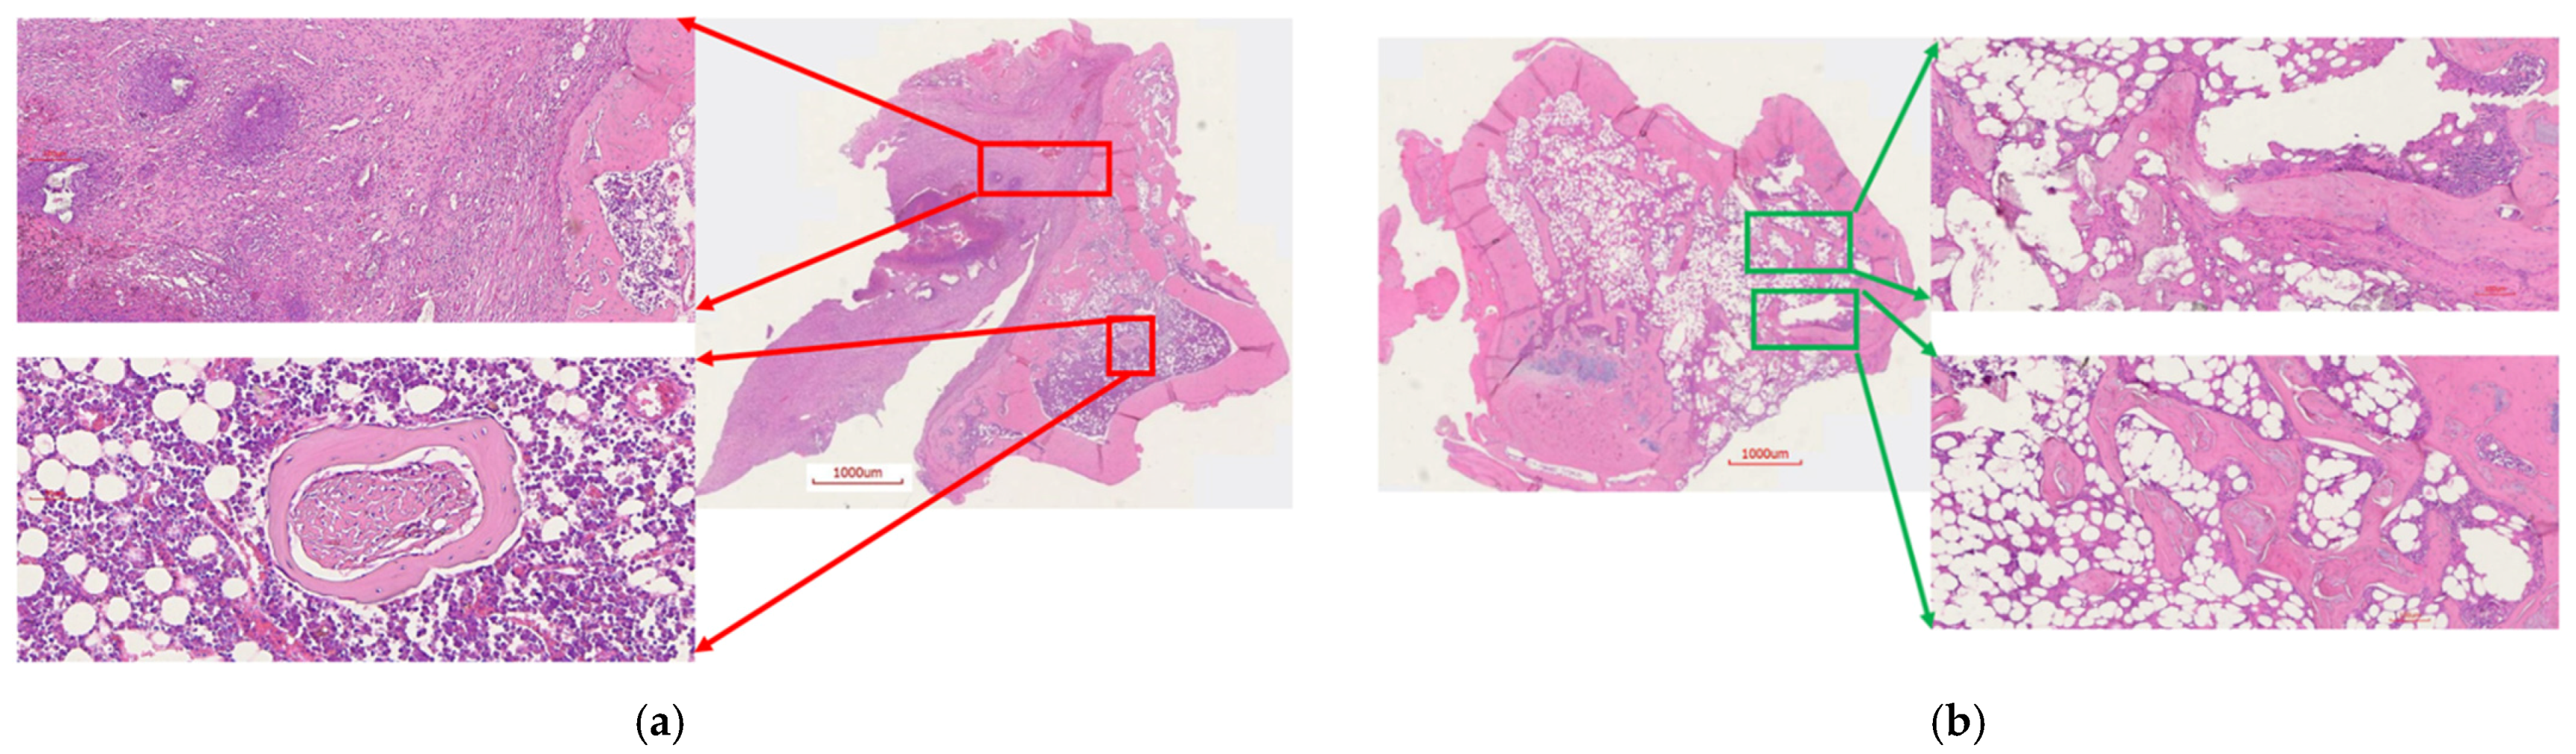

2.6.3. Histology

4.7.4. Histology